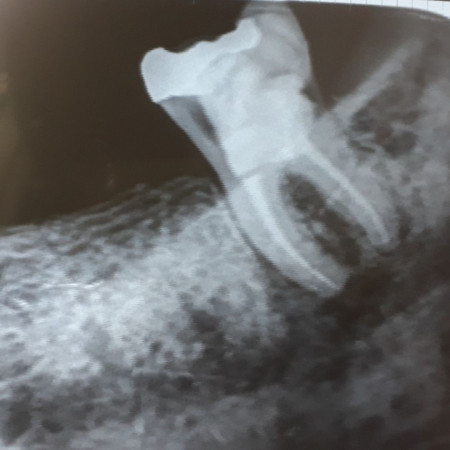

One Visit Root Canal Treatment

When a tooth is infected or the pulp is exposed due to dental trauma, it can be saved by doing a root canal treatment, commonly known as a Nerve filling. 95% of our root canal treatments are completed in one visit, which in turn saves your time and reduces radiation exposure too. We take pride in delivering root canal treatments with minimum post-operative pain and only a very few patients require post-operative use of Antibiotics.

Advanced Complex Root Canal Treatments And Re-treatments

Not all root canal treatments are straightforward. The shape and degree of formation of the root of some teeth require expert intervention. We are proud to house some of the best-trained specialists at Danthaja to handle such cases. Furthermore, failed root canal treated cases done elsewhere, which need re-treatment will also be handled by our specialists.

- MTA treatment cases

- Difficult anatomy cases

- Re-treatment cases